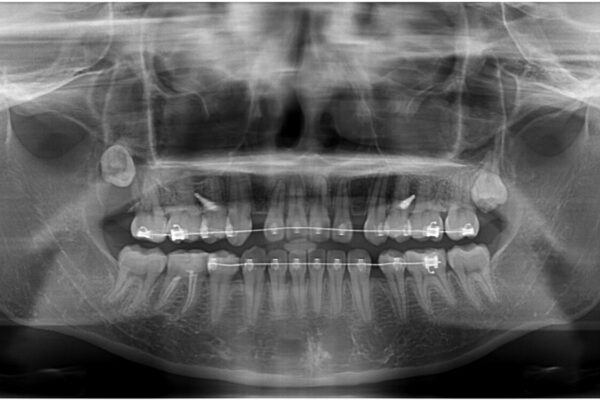

治療途中

• 転勤でも安心して治療継続 抜歯スペース閉鎖と深い噛み合わせ改善のワイヤー矯正 治療途中画像